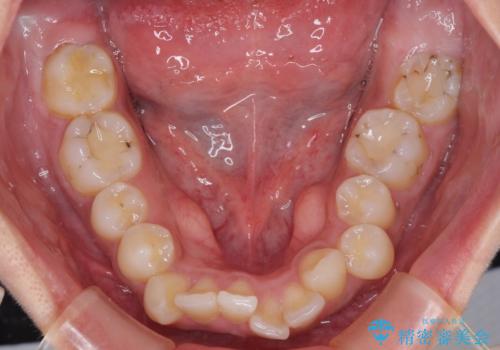

深い咬み合わせと前歯のデコボコ インビザラインによる矯正治療

- 前歯のデコボコと、食いしばりやすい咬み合わせを気にして来院された患者様です。

骨格的に下顎骨が左側に偏位しており、インビザラインでの矯正治療では奥歯の咬みにくさが残る仕上がりが懸念されましたが、新幹線での通院となるため、来院回数の少ないインビザラインでの治療を希望されました。

治療途中では、左右ともに奥歯が咬みにくい状態が続き、問題なく噛めるようになるまでに長期間を要しました。

一方で、デコボコや下顎の前歯が隠れてしまうほどの深い咬み合わせはしっかりと改善されました。